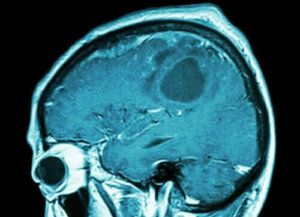

Komt er binnenkort een hersenkankervaccin?

Vaccins zijn een goede manier om ziekten te voorkomen en te genezen. Het is dus heel goed te begrijpen waarom onderzoekers op zoek zijn naar verschillende manieren om een einde te maken aan kankersoorten die zo agressief zijn als hersenkanker. Maar wat als er al een hersenkankervaccin beschikbaar is?

De onderzoekers ontdekten echter dat niet alle tumoren precies hetzelfde zijn en ook niet allemaal goed reageren op immunotherapie. Om deze reden is aan zogenoemde ‘precisie-immunotherapie’ gewerkt om patiënten met glioblastoom te behandelen.

Glioblastoom is een van de kankersoorten met een slechte prognose. Daarom hadden patiënten die eraan leden ten tijde van het onderzoek een persoonlijk vaccin nodig om positieve resultaten te garanderen. Hoe maken experts echter een dergelijk individueel vaccin?